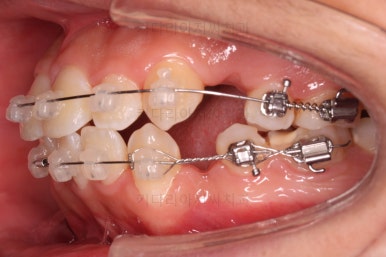

가지런하게 하는 단계를 거친 뒤,당기기 과정에 들어가는데요.

이 과정에서 입이 들어가는 양, 중앙선, 기울기, 앞니 각도 등등 많은 것을 신경써서 당기기를 해주는데요.

이 때 필요한 것이 미니스크류 입니다.

예전과는 다르게 미니스크류를 이용해서 좀 더 정교하고 고난이도의 치료가 가능해지게 된거죠.

다양한 위치/방향/방법으로 치열을 개선해 나갑니다.